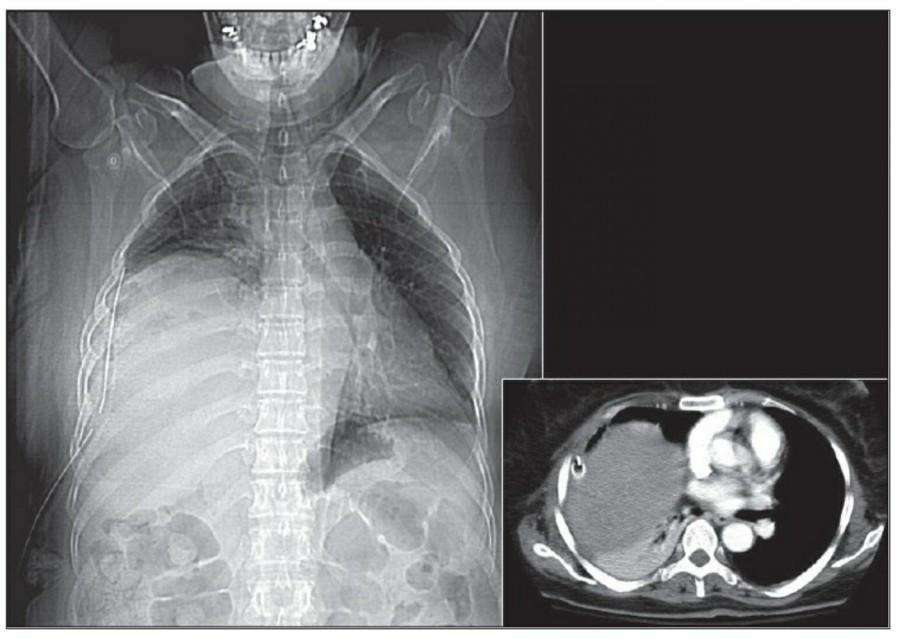

중환자에서 pneumothorax의 진단은 종종 supine radiograph에서 내릴 수 있다. Supine position에서 공기는 anteromedial 방향으로 모이게 되는데, apical air collection이 있을 경우 large pneumothorax가 있음을 시사한다. 공기는 lung과 diaphragm 사이의 subpulmonic location에 trap 되어 있을 수도 있다. 공기가 costophrenic sulcus로 anterolateral extension 될 경우, 이 costophrenic sulcus의 radiolucency를 증가시키는데, 이를 deep sulcus sign이라고 한다. Subpulmonic pneumothorax의 다른 특징으로 diaphragm의 superior surface와 IVC 윗부분이 뚜렷하게 보일 수 있다.

중환자에서 tension pneumothorax의 진단은 매우 힘들다. ARDS와 같은 lung의 병리적인 기전이 lung compliance를 감소시킴으로써 total lumg collapse를 막는다. 또한 tension pneumothorax의 특징인 mediastinal shift가 PEEP으로 인해 나타나지 않을 수 있다. Chest X ray 상에서 tension pneumothorax는 hemidiaphragm의 depression이나 heart border, SVC, IVC의 이동으로 나타날 수 있다.